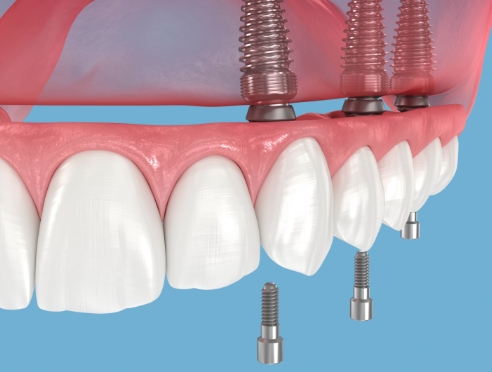

种植牙是在精准诊断与治疗计划的基础上,

通过多个步骤进行的治疗方式

会根据患者的口腔状况, 分阶段安全推进

制定种植位置与手术计划

根据患者状况,

应用个性化种植牙设计

按照预定导板,

稳定植入种植牙